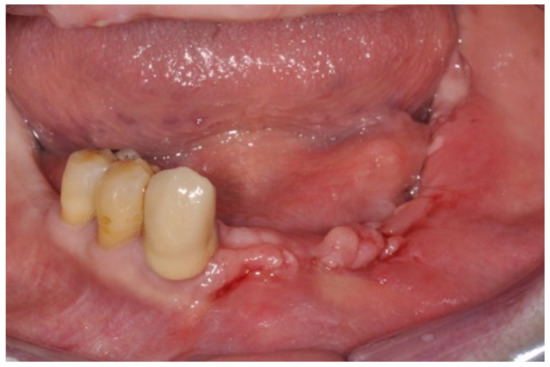

3.1. Clinical Case 1